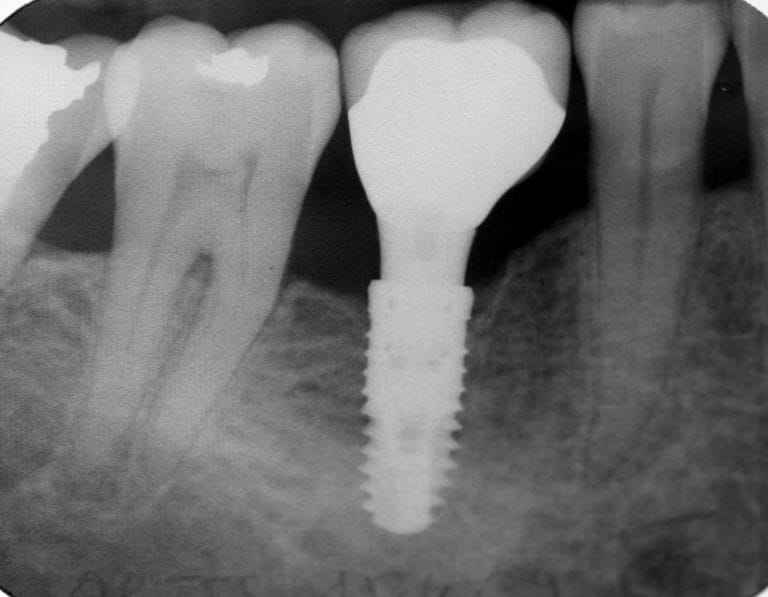

Implant dentaire Lyon : quels sont les composants le constituant ?

Les implants dentaires sont considérés comme des organes dentaires artificiels qui aident à surmonter de manière durable certains problèmes de dentition. En effet, il y a beaucoup de personnes qui souffrent de l’absence d’une ou plusieurs dents en raison de la fragilité de leur dentition naturelle. C’est pourquoi, ces dernières années les chirurgiens dentaires conseillent…